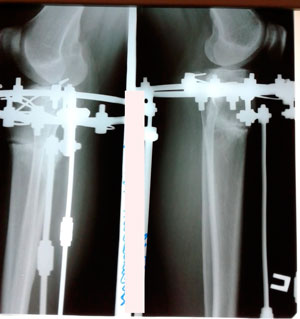

Исходник - 35 лет.

Ротация с обеих сторон.

Дата операции - 08.04.2019г.

Дата снятия аппаратов - 25.07.2019г.

Срок сращения - 105 дней.